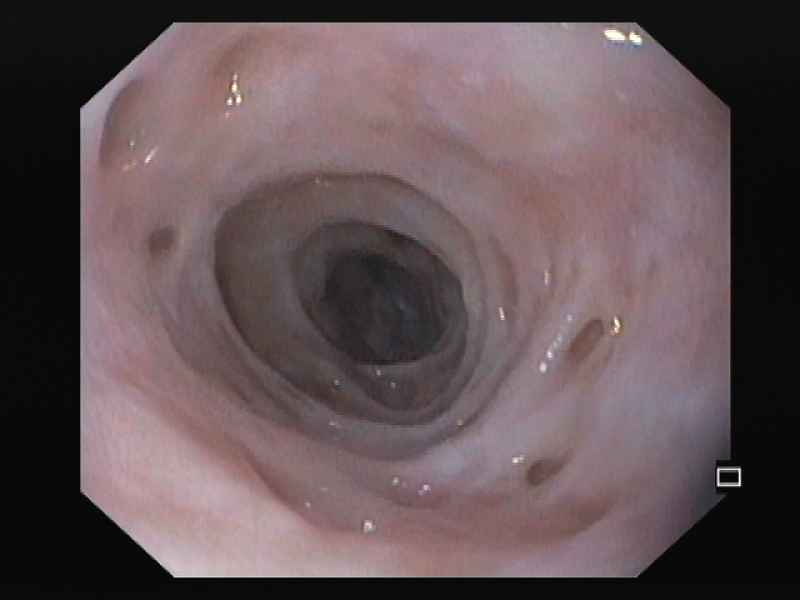

Esophageal Intramural Pseudodiverticulosis – a rare cause of dysphagia

Fotografias